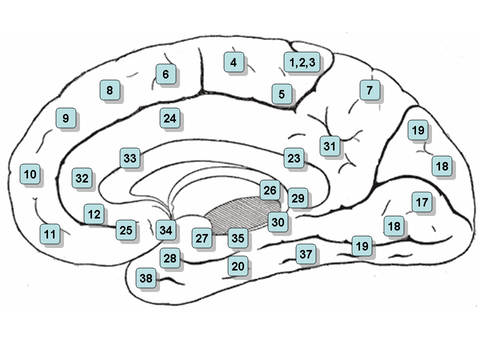

Medial surface of the brain with Brodmann's areas numbered. | |

Human

In the human it and the dorsal entorhinal area 34 (H) together constitute approximately the entorhinal area (Brodmann-1909).